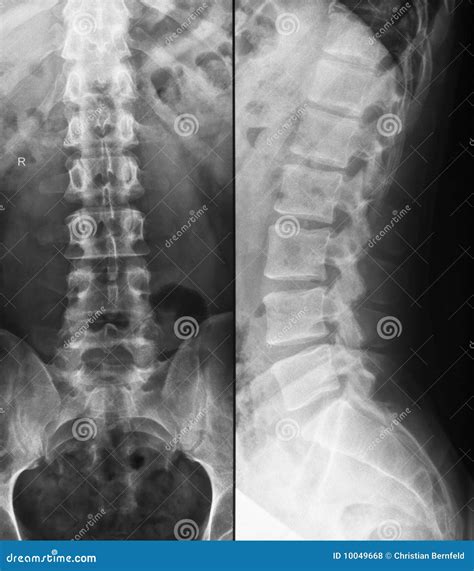

Lumbar Spine Normal X Ray

Understanding the structure of your lower back is essential when dealing with persistent pain or discomfort. When you visit a healthcare provider for lower back issues, one of the first diagnostic tools they often utilize is a Lumbar Spine Normal X Ray. This imaging technique provides a detailed view of the five vertebrae in your lower back, helping physicians rule out fractures, severe alignment issues, or significant degenerative changes. While an X-ray is considered a foundational diagnostic test, understanding what a "normal" result entails can help demystify the process and better prepare you for your medical consultation.

A lumbar spine X-ray is a non-invasive medical imaging test that uses a small amount of radiation to capture pictures of the lower back. It is typically the first line of imaging requested for patients presenting with chronic lower back pain, trauma, or suspected scoliosis. The primary purpose of this exam is to visualize the bony structures, including the vertebral bodies, the intervertebral disc spaces, the facet joints, and the sacroiliac joints.

When a radiologist reviews a Lumbar Spine Normal X Ray, they are checking for structural integrity. They are essentially confirming that the bones are aligned correctly, there are no breaks, and there are no glaring signs of tumors or infections affecting the bone tissue. It is important to note that while X-rays are excellent for looking at bones, they are limited in their ability to show soft tissues like nerves, muscles, or herniated discs.

Key Components of a Normal Lumbar Spine X-Ray

To determine if an X-ray is normal, radiologists look for specific markers of health within the lumbar region. A report will generally indicate that the bones are in their proper place and that no acute pathologies are present. Below are the key components identified in a standard, healthy report:

• Vertebral Alignment: The vertebrae should be stacked in a smooth, gentle curve known as the lumbar lordosis.

• Disc Spaces: These are the gaps between the vertebrae. In a healthy spine, these spaces should be uniform in height, suggesting that the intervertebral discs are adequately hydrated and intact.

• Bone Density: The bones should appear white and dense, without signs of thinning (osteopenia) or unusual spots that could indicate disease.

• Facet Joints: These joints, which connect the vertebrae, should appear smooth with clear boundaries, free from significant arthritic changes.

• No Fractures or Dislocations: The most crucial aspect of a normal report is the absence of any bony breaks or slippage (spondylolisthesis).